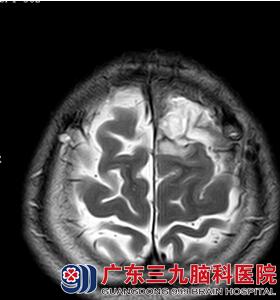

29岁的杨先生,因“发作性意识丧失伴四肢抽搐7天”到广东三九脑科医院就诊。入院前在当地医院检查头颅磁共振示:左侧额叶皮层区异常信号,考虑低级别胶质瘤。

入院后完善术前相关检查及术前准备,由林涛主任在全麻下行左侧额叶肿瘤切除术,手术顺利,术后杨先生的生命体征平稳,神志清楚,术后病理结果回报:星形细胞瘤,WHO II级,术后第十天予头部伤口拆线,伤口愈合良好。